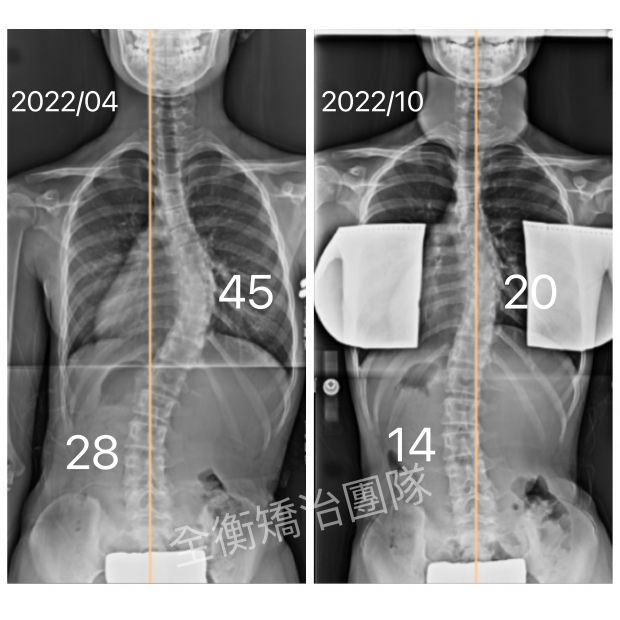

11嵗側彎女生矯正效果媲美手術的祕笈 : 對的時機+對的方法+確實執行11嵗側彎女生矯正效果媲美手術的祕笈 : 對的時機+對的方法+確實執行

11歲脊椎側彎女生,治療(背架+復健運動)半年後,胸椎大彎由45度改善至20度